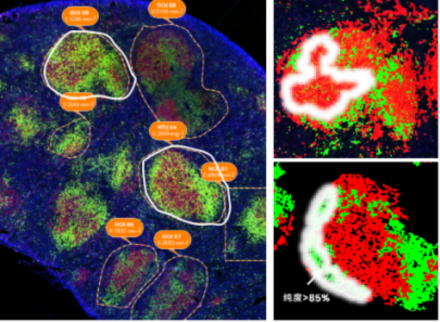

ĪĪĪĪ╗∙ė┌AIūRäeĄ─┐šķg┐╔ęĢ╗»Ż¼īŹ¼F═¼ę╗ÅłŪąŲ¼═Ļ│╔Ė▀Š½£╩Č╚╝Ü░¹ūRäe║═ūįäė╗»ī¦║ĮŪąĖŅŻ╗100%å╬╝Ü░¹╝ēśėŲĘ╩š╝»Ż¼┤_▒ŻČ©ąįČ©┴┐ĮY╣¹Ą─£╩┤_ąįŻ╗Ė▀╔ŅČ╚Ą░░ū┘|ĮMÖz£yĮY╣¹Ż¼0.1 mm2ŪąŲ¼┐╔Öz£y6000+ĘNĄ░░ū┘|ĪŻ

═©▀^ĮY║ŽČÓ╔½├Ōę▀¤╔╣Ō╝╝ągĪó╝ż╣Ō’@╬óŪąĖŅ╝╝ągĪóSISPROTśėŲĘŪ░╠Ä└Ē╝╝ąg║═Ė▀Ęų▒µ┬╩┘|ūV╝╝ągŻ¼īŹ¼Fī”═¼ę╗ÅłŪąŲ¼Ż¼╝╚┐╔▀MąąČÓ╔½├Ōę▀¤╔╣Ō╚Š╔½ś╦ėø╠ž«Éąį╝Ü░¹üå╚║/╣”─▄ģ^ė“Ż¼ėų┐╔ęį═©▀^å╬╝Ü░¹Ęų▒µ┬╩Ą─╝ż╣Ō’@╬óŪąĖŅīó─┐ś╦üå╚║/ģ^ė“ŪąĖŅŽ┬üĒ▀MąąĖ▀╔ŅČ╚Ą░░ū┘|ĮMīWČ©ąįČ©┴┐Ęų╬÷ĪŻ

éĆąį╗»ROIģ^ė“╚”▀xŻ║ņ`╗ŅĄ─ROI╚”▀xŻ¼ūŅ┤¾│╠Č╚ĮŌ╬÷ĮM┐Ś«É┘|ąįĄ─╔·╬’īWęŌ┴xĪŻ

Ė▀śėŲĘ╩š╝»┬╩Ż║╝ż╣Ō’@╬óŪąĖŅ║¾śėŲĘĄ─╩š╝»═¼śėųžę¬Ż¼žÉŲšŖW╔·╬’┐╔īŹ¼FÄū║§100%Ą─śėŲĘ╩š╝»Ż¼ūŅ┤¾Ž▐Č╚╣Ø╩Ī┼R┤▓šõ┘FśėŲĘĪŻ

═©▀^ī”ąĪ╩¾Ųó┼KĄ─FFPEŪąŲ¼▀Mąą├Ōę▀¤╔╣Ō╚Š╔½Ż¼Ęųäeś╦ėøB╝Ü░¹ĪóT╝Ü░¹Ż¼0.1 mm2Š∙ĶbČ©ĄĮ7600+ĘNĄ░░ū┘|Ż¼PCAĘų╬÷▒Ē├„ā╔éĆģ^ė“ėą├„’@▓Ņ«ÉŻ¼ūC├„┐šķg┐╔ęĢ╗»Ą░░ū┘|ĮMīWĘĮ░ĖĄ─ėąą¦ąį║═Ė▀ņ`├¶Č╚ĪŻ